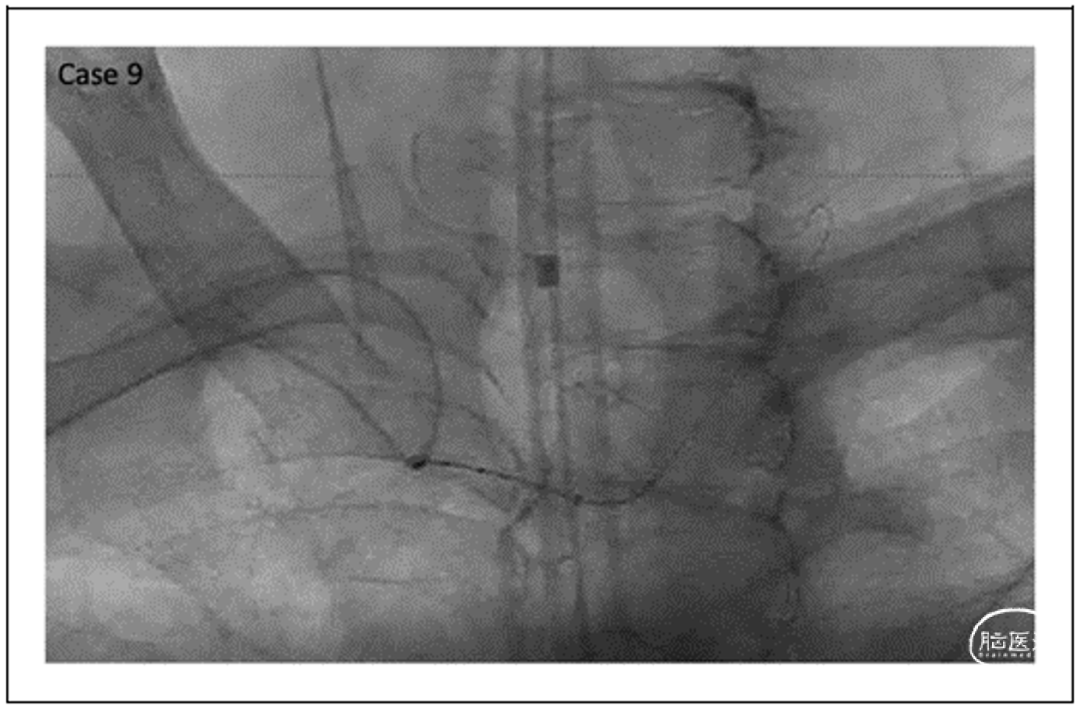

结果

病例集锦